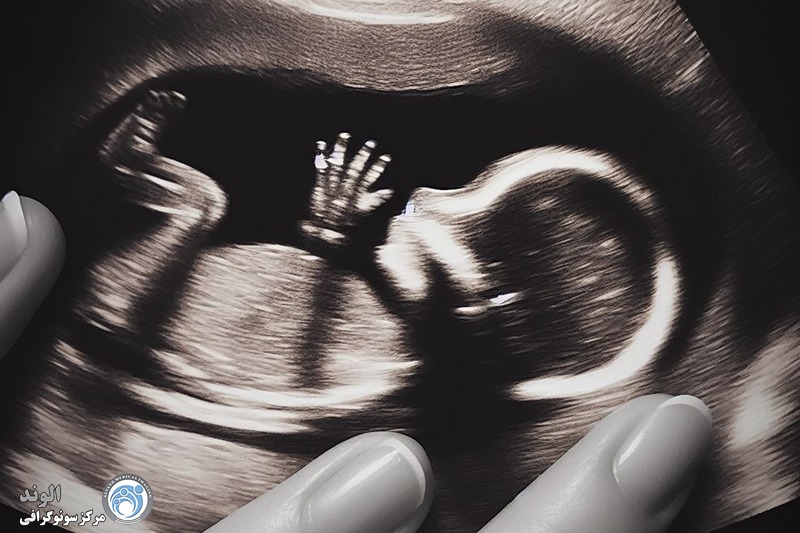

بین 17 تا 22 هفته، ما اغلب یک ارزیابی سونوگرافی از جنین انجام می دهیم تا آناتومی آن را از نزدیک ببینیم. این اسکن می تواند به ما بگوید که آیا مغز به درستی رشد کرده است، آیا شکاف لب، ناهنجاری قلبی و البته جنسیت جنین وجود دارد یا خیر.

آنومالی اسکن یا سونوگرافی سطح دوم، یک بررسی دقیق از آناتومی جنین است که معمولاً بین هفتههای ۱۸ تا ۲۲ بارداری انجام میشود. در این مرحله از رشد جنین، بسیاری از اندامها به اندازهای رشد کردهاند که میتوان ساختار آنها را به وضوح مشاهده و بررسی کرد. این سونوگرافی برخلاف اسکنهای اولیه که بیشتر برای تعیین سن بارداری یا بررسی ضربان قلب انجام میشوند، تمرکز اصلیاش بر شناسایی ناهنجاریهای ساختاری در جنین است.

اندامها: بررسی دستها، پاها و انگشتان.